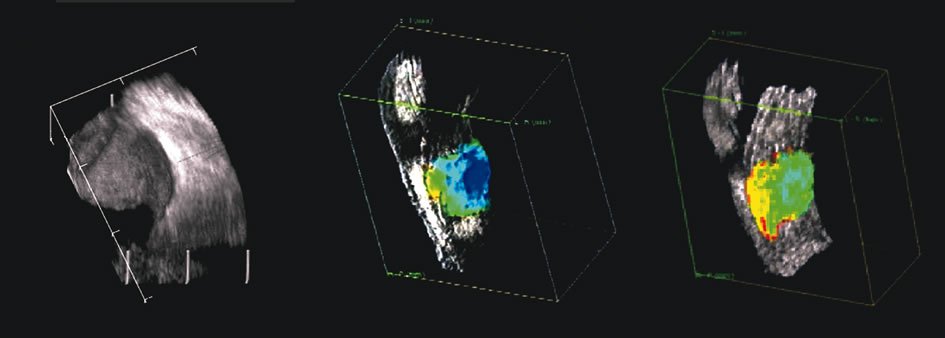

The representation of volume and three-dimensional perspectives of the diseased vitreous, retinal detachment, choroidal detachment, and tumors can add to presurgical conceptualization and is critical to characterization of tumors in relation to prediction of lethality.45 In addition, volume measurement of the choroid permits studies of both surgical and physiologic rates of clearance of hemorrhage, whereas vitreous volume studies can make the estimation of gas or other vitreous substitutes for replacement more accurate (Fig. 25).

Fig. 25. A 3D reconstruction of serial scans of a posterior pole melanoma taken with a 10 MHz transducer (left) shows the extent and relative asymmetry of the tumor within the vitreous cavity. 3D biometry can be useful for treatment planning for radiotherapy and brachytherapy. 3D reconstructions of 50 MHz serial ultrasound scans and parameter images of a melanoma involving the ciliary body and anterior uvea (center, right) before and after treatment with combined ultrasound hyperthermia and brachytherapy. Changes in the concentration of ultrasound scattering elements related to tissue necrosis are seen as color scale in the pre- and postimage region of the tumor shifts, from blue, indicating relatively low acoustic concentration, to yellow and green, indicating higher concentrations of scatterers.

Spectral parameter imaging, a digital signal processing technique that examines the frequency content of backscattered ultrasound signals, has been shown to be predictive of increased lethality in certain patients and also to be useful in the in-vivo identification of high-risk melanomas for treatment staging.46–48 The shape, density, orientation, and number of scattering elements in a region influence not only the relative amplitude or brightness of a pixel on B-scan but the frequency content of the signal returned to the transducer.19 The concept of differentiating tissue backscatter in a quantitative manner rather than in simple qualitative descriptions of hypo-, iso-, and hyperechoic variations in gray scale allows for maximum use of information available in the digital ultrasonograms. These techniques can be extended to examining the functional anatomy of the eye as well as disease states other than solid tumors (Fig. 26).